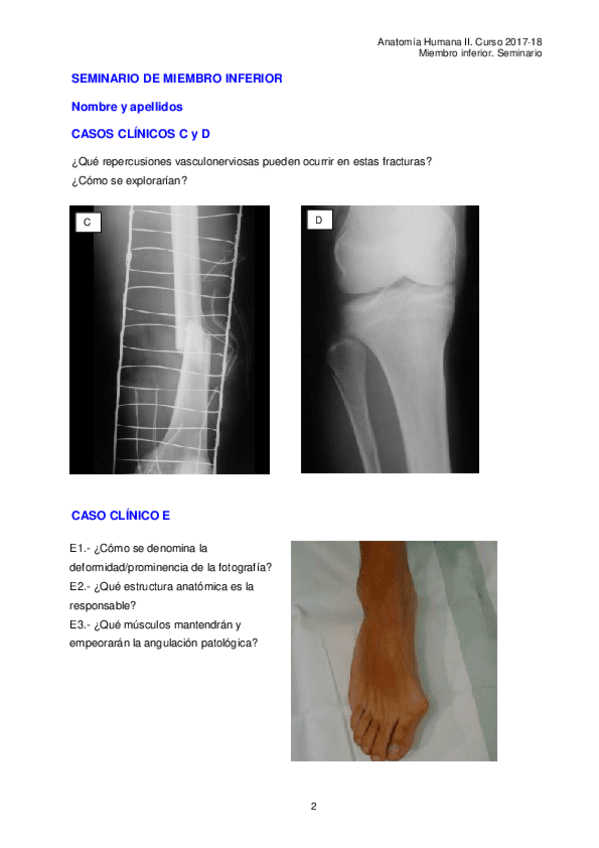

He publicado nuevos apuntes de 1º Anatomía Humana II: Miembro-inferior.-Seminario.pdf